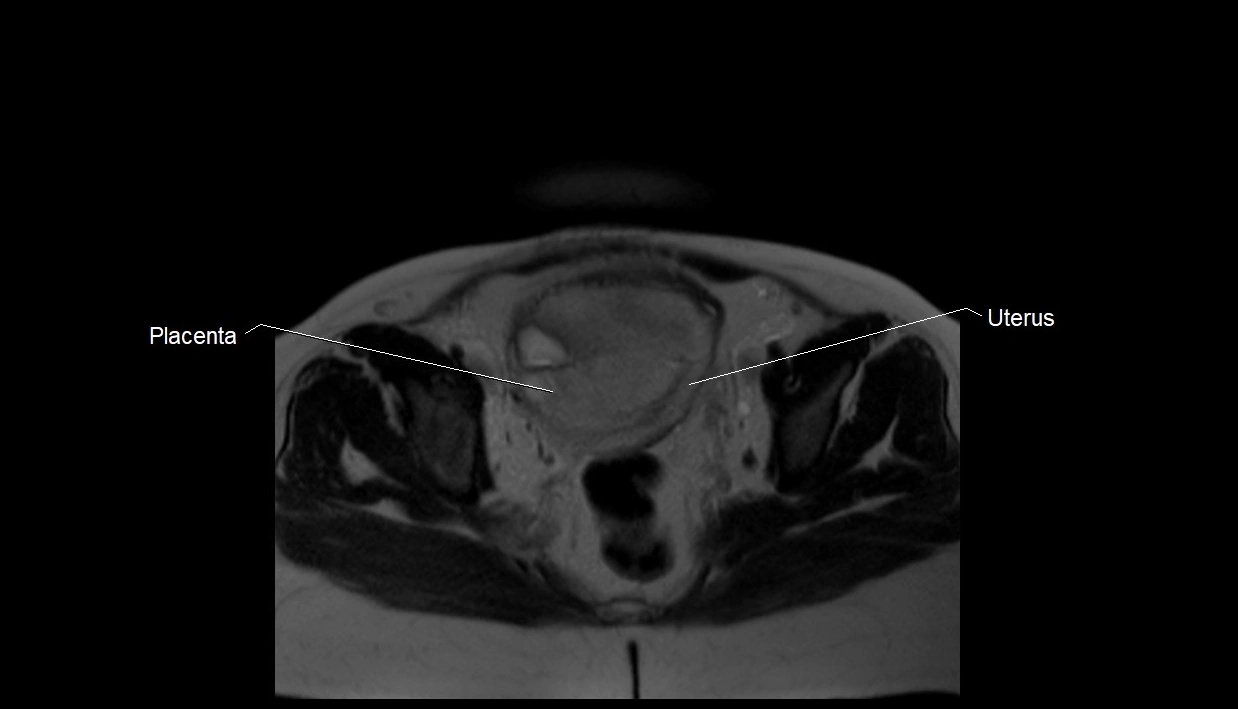

MRI image

image